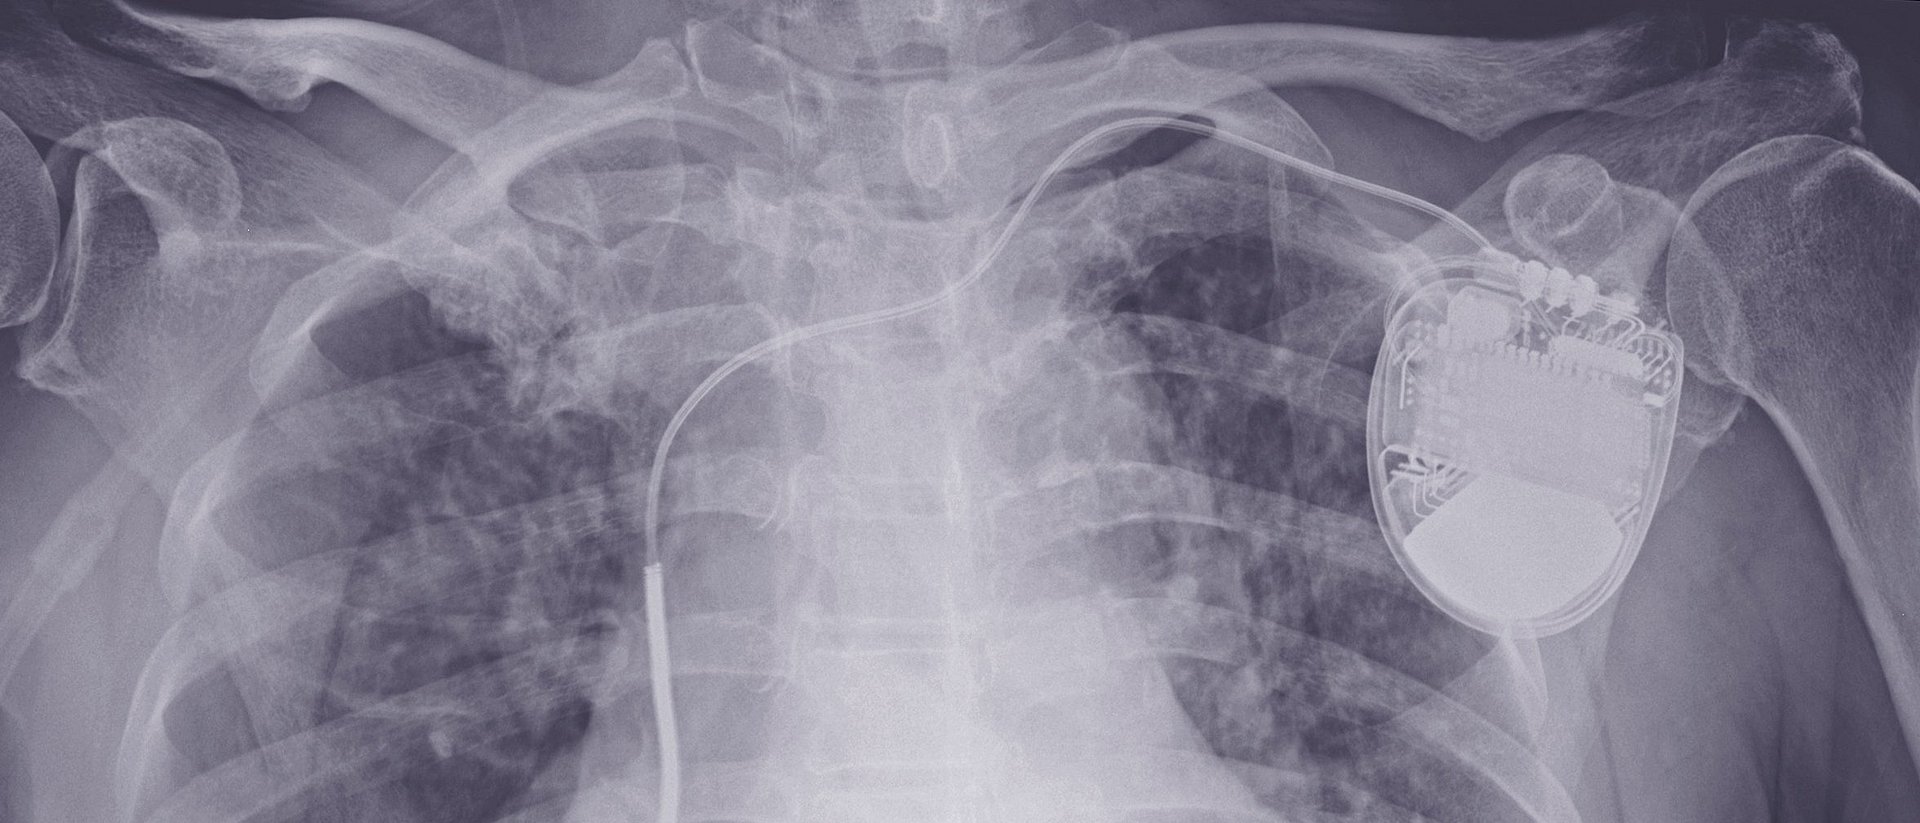

In heart patients with potentially life-threatening arrhythmias, a strong electrical shock applied to the cardiac muscle can reset the heart to its regular rhythm. This is precisely the task of defibrillators, which are inserted into the chest like pacemakers. Under current guidelines, physicians implant these devices as a preventive measure in patients with certain heart conditions. The procedure is performed more than 100,000 times per year in the EU. Apart from the high costs for the health care system, the devices also pose a risk: According to estimates, one in four implanted defibrillators will lead to significant complications within ten years – from infections to spontaneous electric shocks.

The EU-CERT-ICD study therefore examined the benefits of prophylactically implanted defibrillators throughout Europe. In a sub-study of the EU-CERT-ICD project, the scientists led by first author Prof. Axel Bauer (formerly LMU and currently Medical University of Innsbruck) and the two co-senior authors Prof. Georg Schmidt (TUM) and Prof. Markus Zabel (University Medical Center Göttingen) wanted to identify the patients who benefit most from the operation.

The preventive implantation of a defibrillator resulted in an overall 43 percent decrease in mortality over the subsequent four-year period. For patients with a PRD value greater than or equal to 7.5 degrees, the reduction in the mortality risk was significantly larger, at 75 percent. For PRD values below 7.5 degrees, the mortality risk was reduced by only 31 percent. “PRD could become an important decision making tool for physicians,” says Georg Schmidt, the head of the Biosignal Processing Working Group at TUM's Klinikum rechts der Isar. “With the additional information, patients who would probably not benefit from a defibrillator could be spared the risk of an implant. Instead we could focus on those whose lives would likely be extended by the device.” The results will first have to be confirmed in further studies, however, before they can be included in medical treatment guidelines. “An important step, among others, would be to conduct a study over a longer period,” says Markus Zabel, the head of the main EU-CERT study.